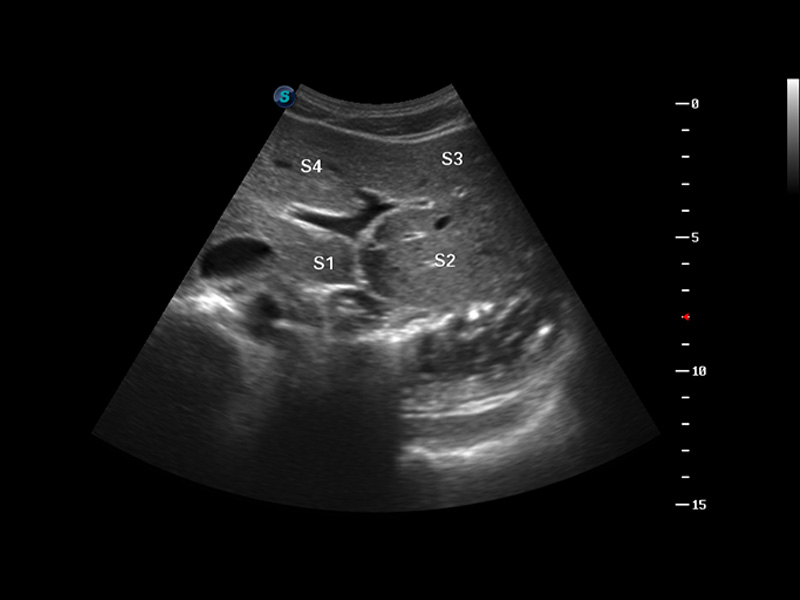

S8 EXP便携式彩色多普勒超声诊断仪是竞技宝(JJB)官方网站研发的高端全身应用型便携彩超。高通道的VIS平台融合可视化(Visual)、智能化(Intelligent)和人性化(Smart)的特点,配以竞技宝(JJB)官方网站自主研发生产的探头大家族,使您能够快速、准确的获得病人信息,提高工作效率的同时减轻疲劳。

谐波成像